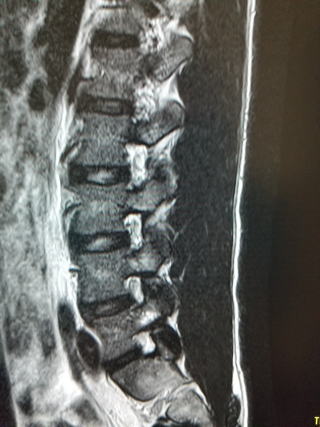

新鮮腰椎分離症 原因は疲労骨折とされます。 MRI:T2強調像L5左側椎弓に高信号あり 新鮮例は小中学生で多く、高校生では進行例、陳旧例が多い。成人ではほぼ陳旧例ですが、まれにハイアスリートで新鮮例があります。 新鮮例と一部の進行例は適切な治療により治すことができます。年齢が低いほどすべり症を併発するので注意が必要です。早期の診断はMRIで行います。早期のものはレントゲンでは分かりません。 |

腰椎椎間板ヘルニア ヘルニアの大きさと症状は一致しませんが、腰痛や下肢痛、しびれの原因となります。椎間板の変性によって起こります。大切なことはヘルニアの位置と症状が一致するかどうかです。大きなヘルニアでも無症状のことがあります。画像だけで早合点してはいけません。 早ければ中学生ぐらいで発症します。椎間板ヘルニアの90%は平均4ヶ月で吸収され縮小します。大きなものは一年ほど掛かります。残りの10%は吸収されずに残ります。このことが分かってからは手術することが随分と少なくなりました。 手術適応は膀胱直腸障害を起こすもので溢尿や尿閉を来す場合は48時間以内の緊急手術が推奨されています。また保存治療に抵抗する強い痛み、しびれ、麻痺がある場合も手術を考慮しますが、絶対しなければならないものではなく、相対的手術適応とされご本人の希望により行います。 足の裏などに生じるしびれ感は手術をしても改善しにくいことは知っておいてください。 保存治療はお薬や理学療法、腰痛体操、運動療法などを組合せて行います。発症すると慌てて腹筋、背筋などの筋トレを始める方がありますが、病状により返って悪化することもありますのでご注意ください. |